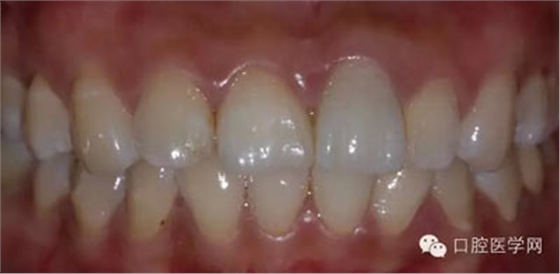

5、3MU200樹(shù)脂粘接劑粘固全瓷冠術(shù)后照

6、術(shù)后一周照,牙齦恢復(fù)良好